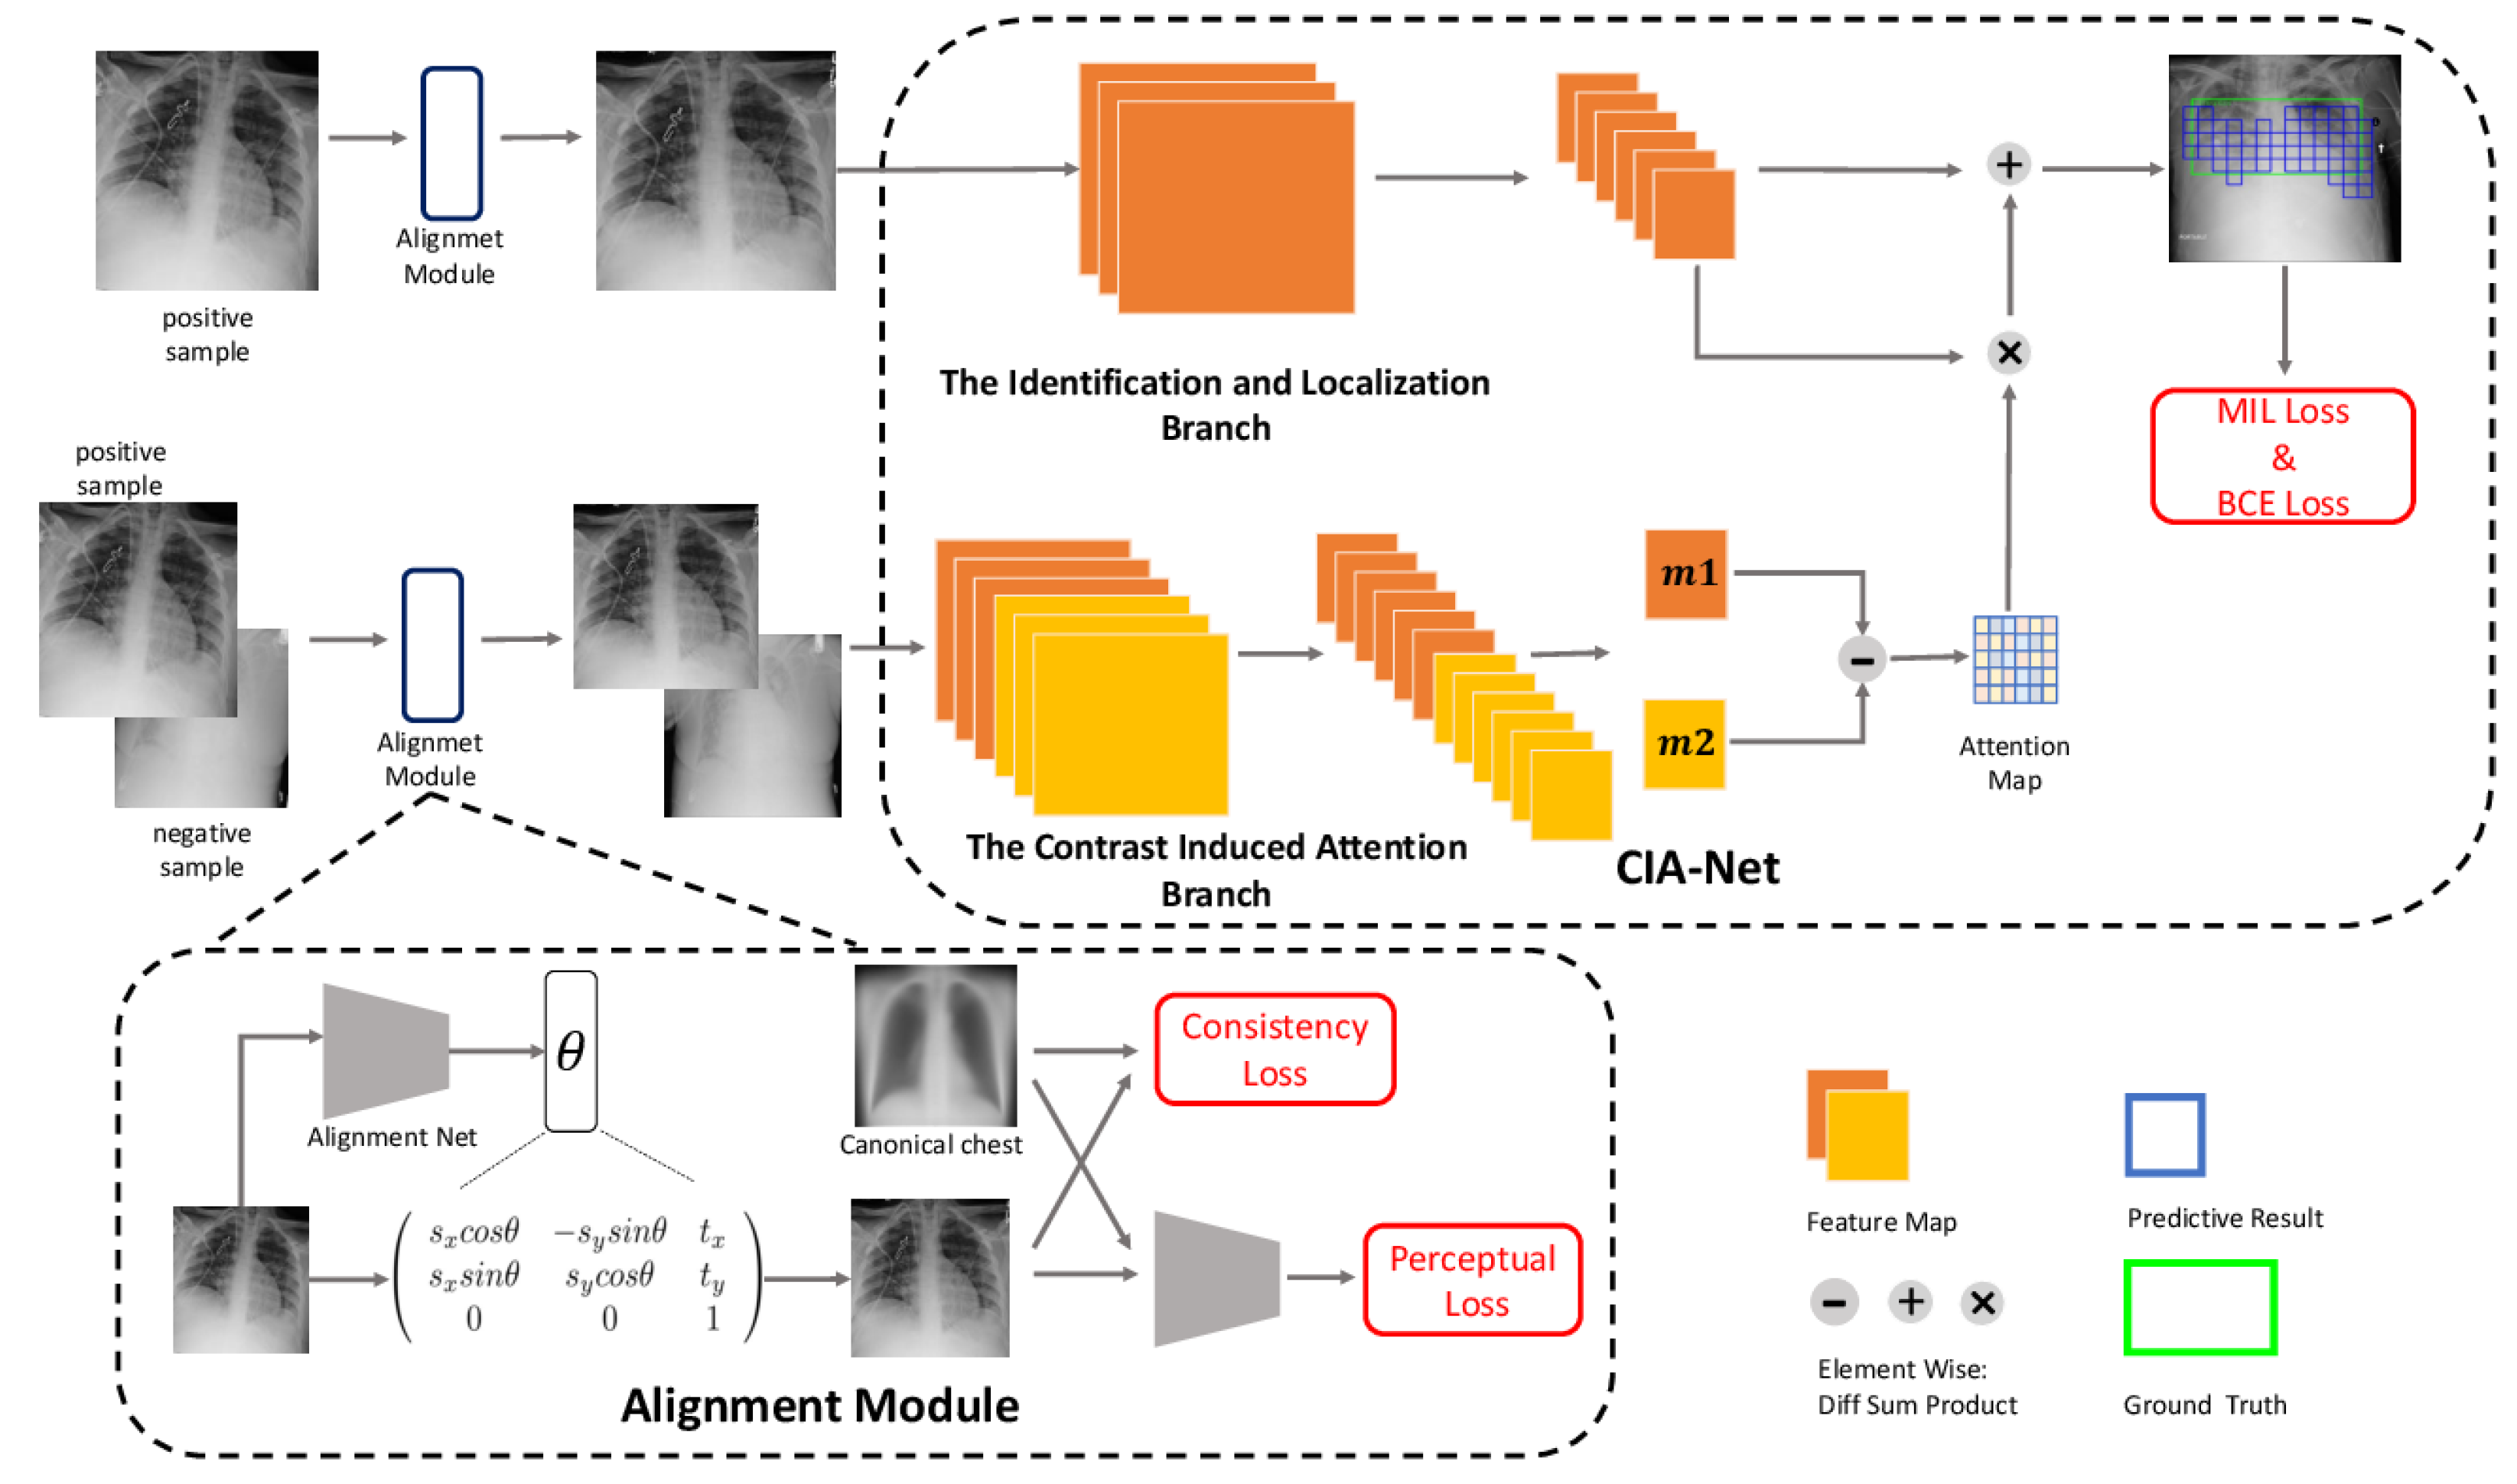

- Liu, J.; Zhao, G.; Fei, Y.; Zhang, M.; Wang, Y.; Yu, Y. Align, attend and locate: Chest X-ray diagnosis via contrast induced attention network with limited supervision. In Proceedings of the IEEE/CVF International Conference on Computer Vision, Seoul, Republic of Korea, 27 October 27–2 November 2019; pp. 10632–10641. [Google Scholar]